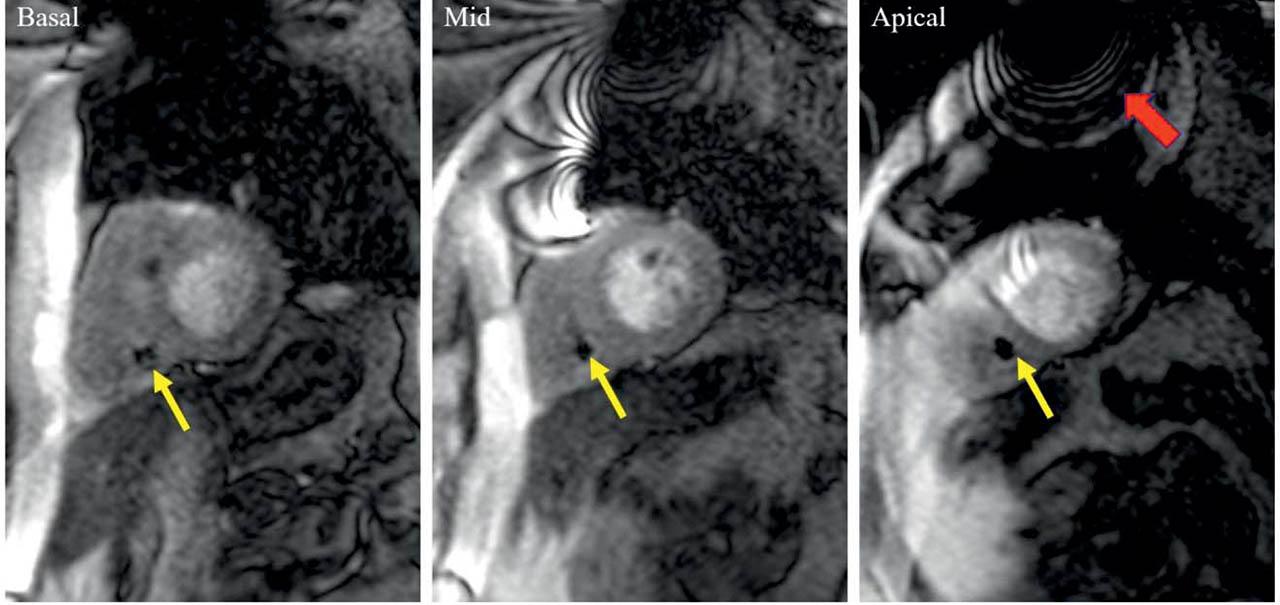

Figure 4